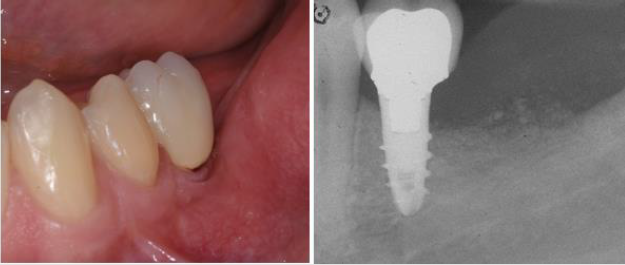

(Biaggini Medical Devices, Arcola, Italy), the ridge showed now a width of 7 mm as compared to the 2 mm at baseline (Figure 10). Three months later the implant was exposed and a healing abutment was connected associating and apical repositioned flap in order to replace the keratinized gingiva buccal to the abutment (Figure 11) One month after complete maturation of the soft tissue impressions were taken in order to fabricate a ceramic crown (Figure 12). Final restoration was delivered about nine months after the beginning of treatment (Figures 13&14) but the radiograph and the clinical picture show how the primary objectives of treatment were met. Bone augmentation in order to accommodate a standard diameter implant in order to re-establish function and proper occlusion. A three year follow up shows a perfect stability of the regenerated area (Figure 15) [5].